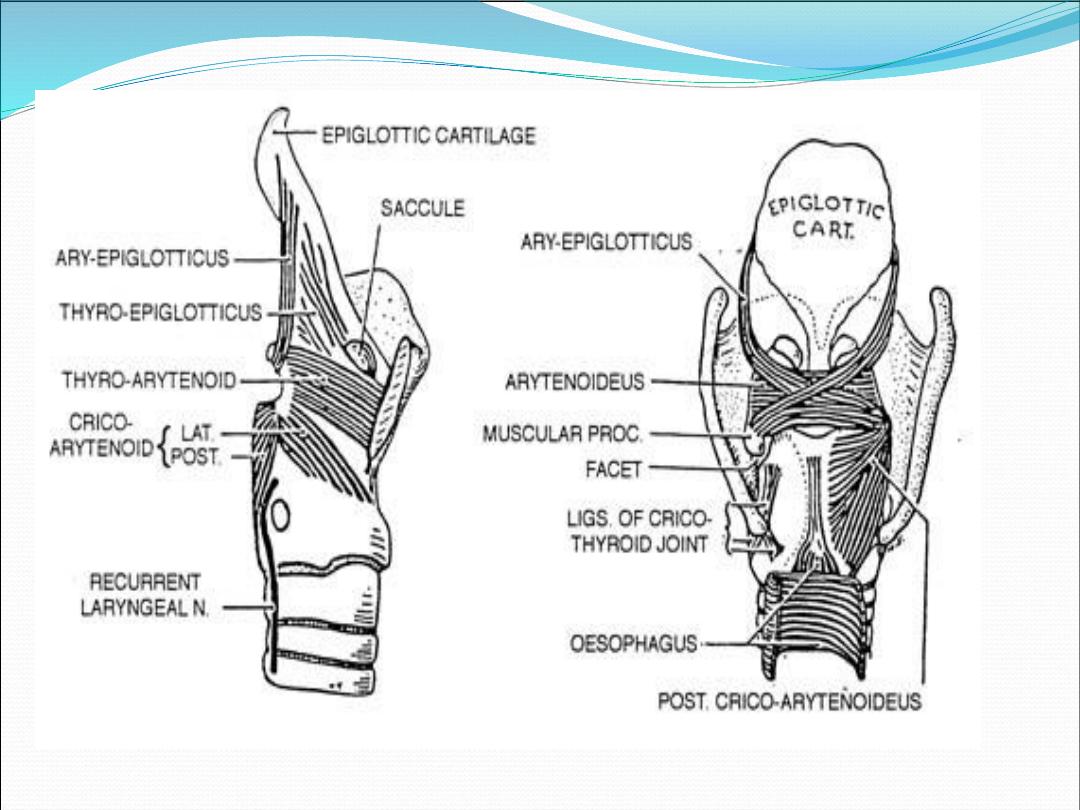

Extrinsic m.

•

Sternohyoid muscle

•

Thyrohyoid m.

•

Geniohyoid m.

•

Stylohyoid m.

Intrinsic muscle

•

Thyroarytenoid m.

•

Interarytenoid m.

•

Posterior cricoarytenoid m.

•

Lateral cricoarytenoid m.

•

Cricothyroid m.